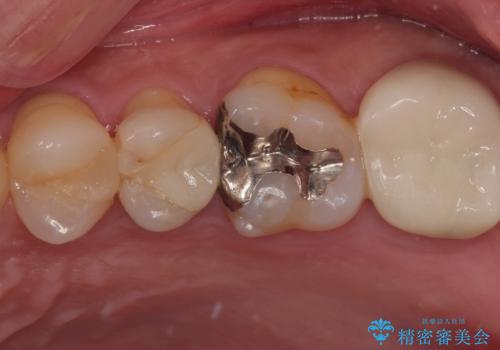

- 歯の間に物が詰まるとのことで来院された患者様です。以前に歯冠部の神経の一部を取り除き、MTAセメントという特殊なセメントを充填し、歯根部の神経を温存する生活歯髄療法(VPT)を行われておりセラミックの詰め物にて修復されていました。セラミックの詰め物が少し欠けたことにより食べ物が挟まってしまう状況でした。

まず神経の生活反応を確認し、今回はセラミックの詰め物のやり替えではなく、セラミックのかぶせ物で治療を行っていくこととしました。

拡大鏡視野下で、セラミックの詰め物、虫歯の除去を行い、オールセラミッククラウンに適した形に整えました。